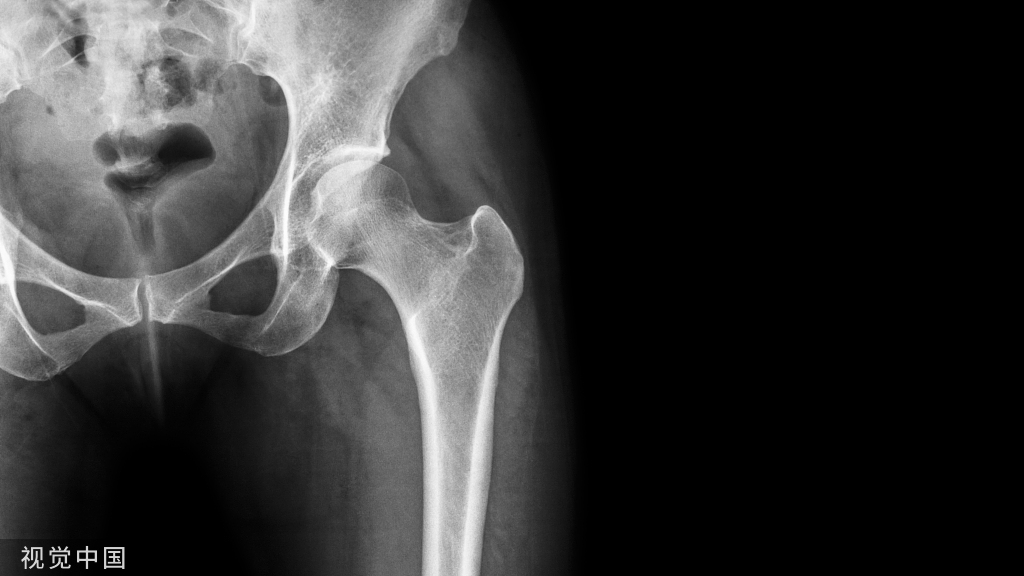

病例一、无症状距后三角骨男,49岁,因扭伤踝部来院就诊,X线片提示:踝部骨折。